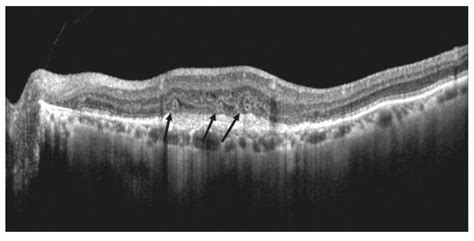

For individuals facing the risk or diagnosis of vision-threatening conditions, Optical Coherence Tomography (OCT) has revolutionized the way eye care professionals monitor retinal health. When it comes to Optical Coherence Tomography Macular Degeneration, this non-invasive imaging technology serves as the gold standard for both early detection and long-term management. By providing high-resolution, cross-sectional views of the retina, OCT allows ophthalmologists to visualize the microscopic layers of the macula, identifying subtle changes long before they manifest as significant vision loss.

OCT works similarly to an ultrasound, but instead of using sound waves, it utilizes light waves to capture images. Because light travels much faster than sound, OCT can achieve a level of detail that is nearly equivalent to an optical biopsy. When a patient undergoes an OCT scan for suspected Optical Coherence Tomography Macular Degeneration, the device measures the reflection of light from the various layers of the retina.

• Identify the presence and size of drusen.

• Measure retinal thickness to track atrophy over time.

One of the most critical aspects of Optical Coherence Tomography Macular Degeneration management is the ability to detect disease activity before the patient experiences symptomatic vision changes. In the “dry” stage, OCT can highlight the presence of intermediate drusen, prompting more frequent monitoring. In the “wet” stage, the immediate detection of fluid accumulation allows for timely intervention, which is vital for preserving remaining vision.